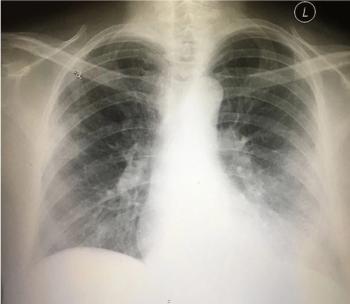

A 66-y/o man presents with worsening generalized headache x2 days plus chills and dry cough. Initial concerns: encephalitis, influenza, URI, pneumonia? Your Dx?